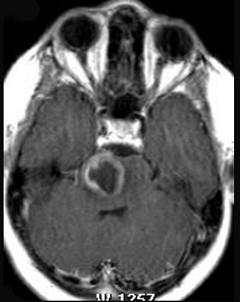

问题 脑干肿瘤(如图所示)最多见的是()

选项 A.星形细胞瘤 B.室管膜瘤 C.胶质母细胞瘤 D.海绵状血管瘤 E.血管网状细胞瘤

答案 A